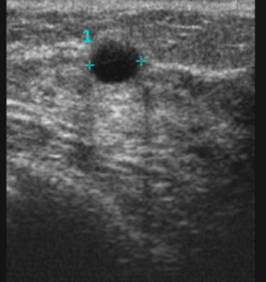

La ecografía de mama es una técnica de diagnóstico que consiste en la visualización de una imagen.

Se realiza con el ecógrafo que consta de un transductor; éste utiliza los ultrasonidos para que podemos ver a través de la pantalla toda la estructura de la mama.

A través de la ecografía veremos la estructura de la mama internamente como: piel, tejido mamario, conductos mamarios, músculo y costillas. Además de la estructura de la mama podemos encontrar lesiones que pueden ser sólidas o líquidas siempre y cuando éstas no sean muy pequeñas. También podremos ver la localización, el número, el tamaño y forma de las lesiones.